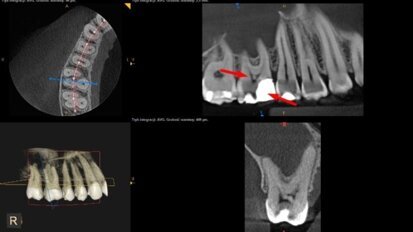

„3D w endodoncji – jak diagnozować i leczyć bezpiecznie” – webinarium DT Study Club!

Dental Tribune Study Club zaprasza do udziału w webinarium, które odbędzie się w poniedziałek 5 grudnia o godz. 20.00. Wykład pt.: „3D w ...